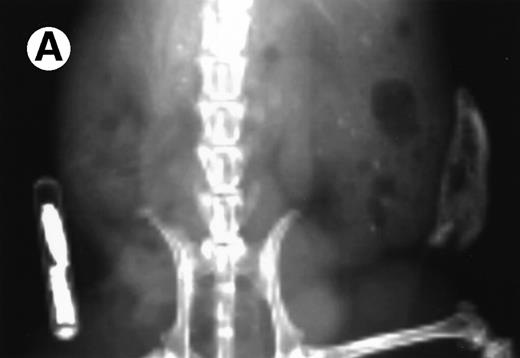

Loss in density of human bone in myeloma-bearing SCID-hu mouse as seen by x-radiography. Human bones are visible in the right-hand side. The highly contrasted devices visible in the bottom left corner are implant transponders used to identify the mice. (A) Myeloma-bearing mouse (patient no. 6): (B) Age-matched control SCID-hu mouse.